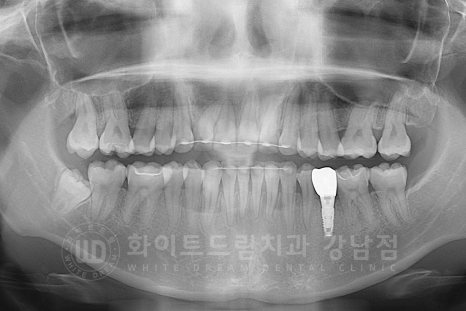

식립된 임플란트의 치유 과정을 살피면서 치아교정 진료도 마무리에 접어들게 됩니다.

총 치료 기간 : 15.08.01 - 17.09.22

임플란트 & 치아교정을 동시 진행하는데, 2년 정도의 시간밖에 소요되지 않았는데요.